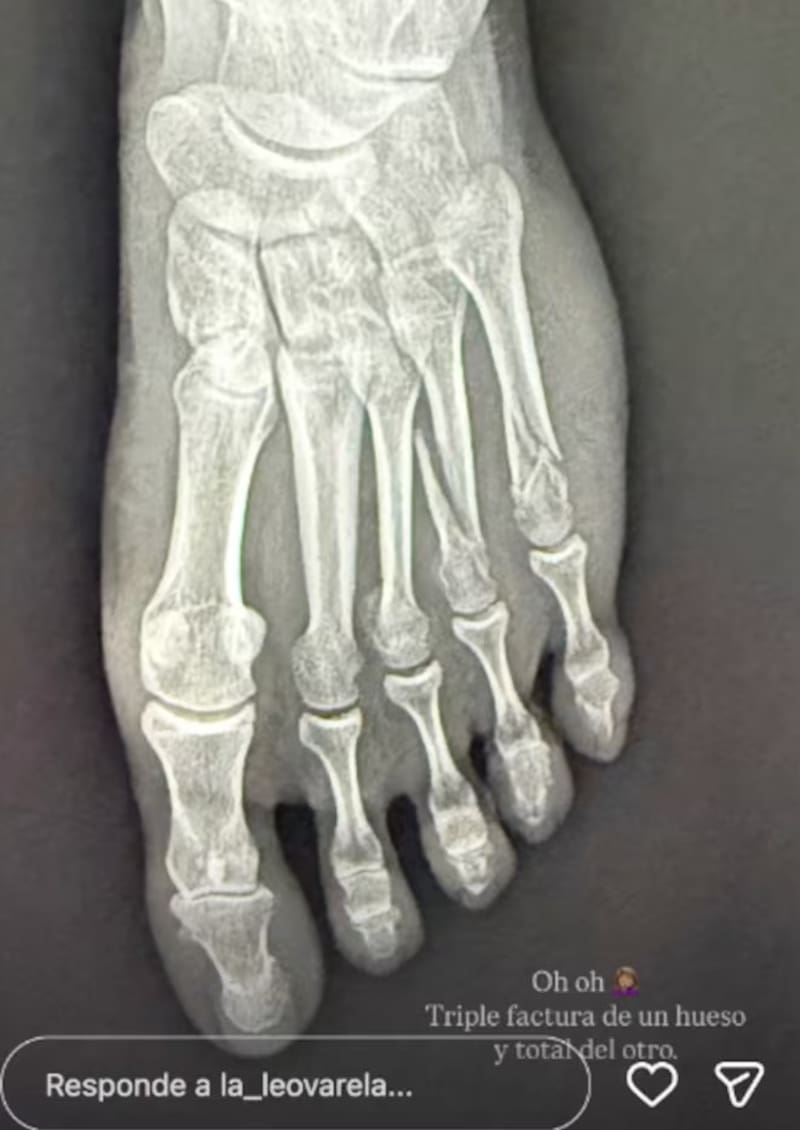

Junto a una foto de una radiografía de su pie, la actriz señaló: “Oh, oh. Triple fractura de un hueso y total del otro”.

“No vi el escalón de la pieza”, escribió en el posteo, junto a una foto de su pie, que se aprecia muy hinchado.